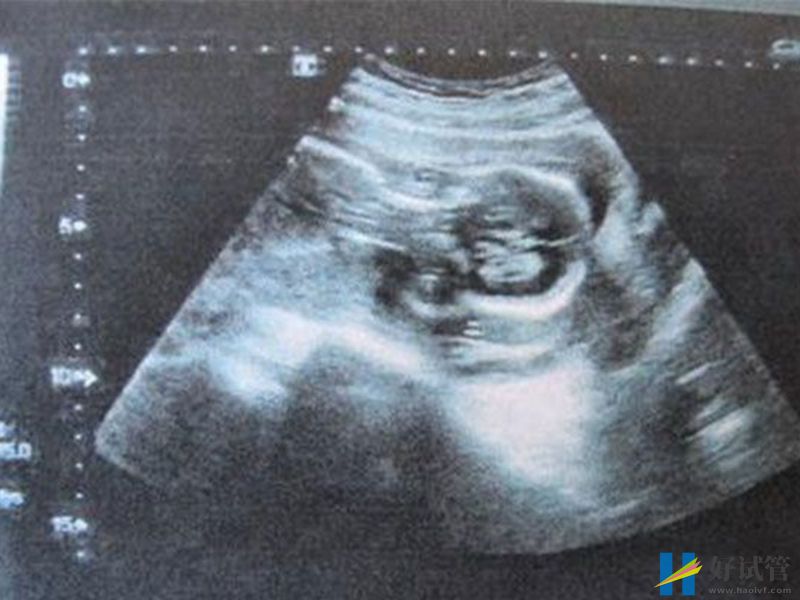

nt值2.9mm不正常!胎儿可能存在先天性疾病

根据国内各大医院检查准则来讲,nt值的正常范围应该是在2.5mm之下,所以说2.9mm的nt值已经超出了正常范围,这个数据在一定程度上说明胎儿存在先天性疾病的风险。

虽然在理论上2.9mm的确超出了范围,但是胎儿的正常与否不能单单凭借着nt值就能确定,此时孕妇也不要有心理压力,nt检查流程的进行只是作为一项排畸检查的预警检查,其结果也只是粗略估计,并不能直接作为确诊依据,想要确认胎儿是否已经患病或者存在畸形,进行进一步检查如唐筛、羊水穿刺或无创DNA是十分有必要的。